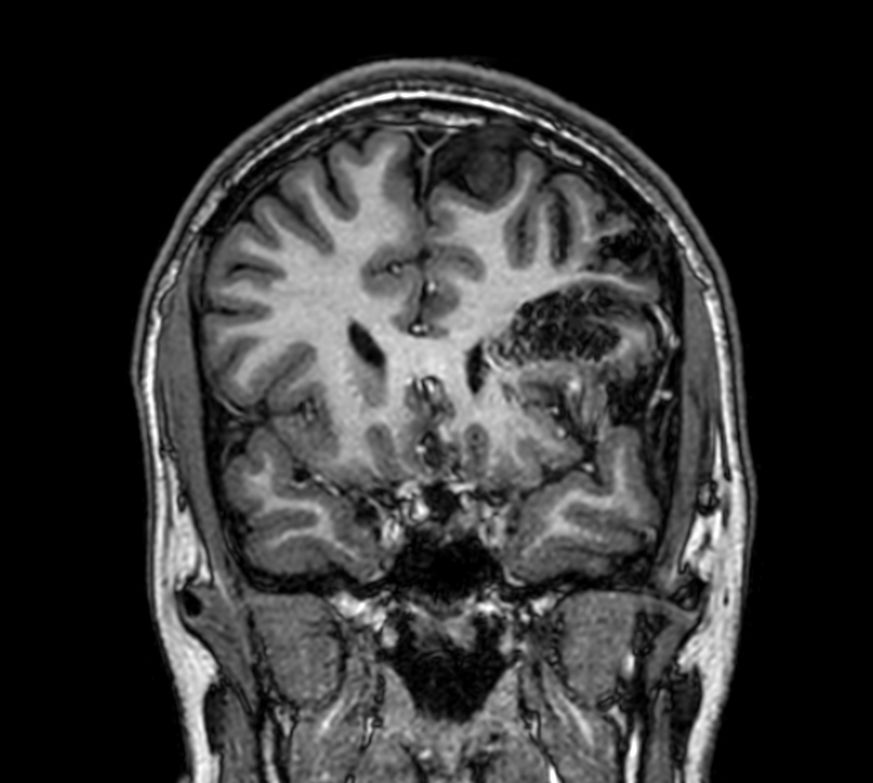

Pediatric brain with AVM

Pediatric patient with frontal brain AVM. MultiVane XD is used to achieve high resolution diagnostic images, even in the case of severe patient motion. SWIp sequence is added to acquire exquisite susceptibility contrast. The 3D sequences with isotropic voxel size enable reformats in any plane without loss of resolution. And 4D-TRAK XD, a fast, dynamic contrast-enhanced MR Angiography method allows to achieve high spatial and temporal resolution simultaneously. Integration of Compressed SENSE acceleration technique enables speeding up of the entire exam.

3D T1w TFE - Coronal reformatCompressed SENSE